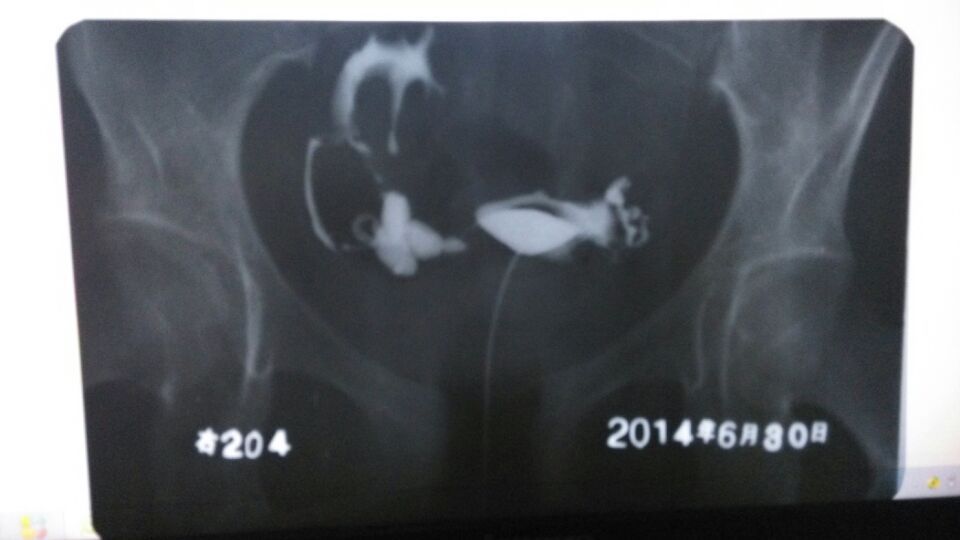

求专家看看输卵管造影拍的片子,昨天做造影的时候很痛

做输卵管疏通要多少钱呢